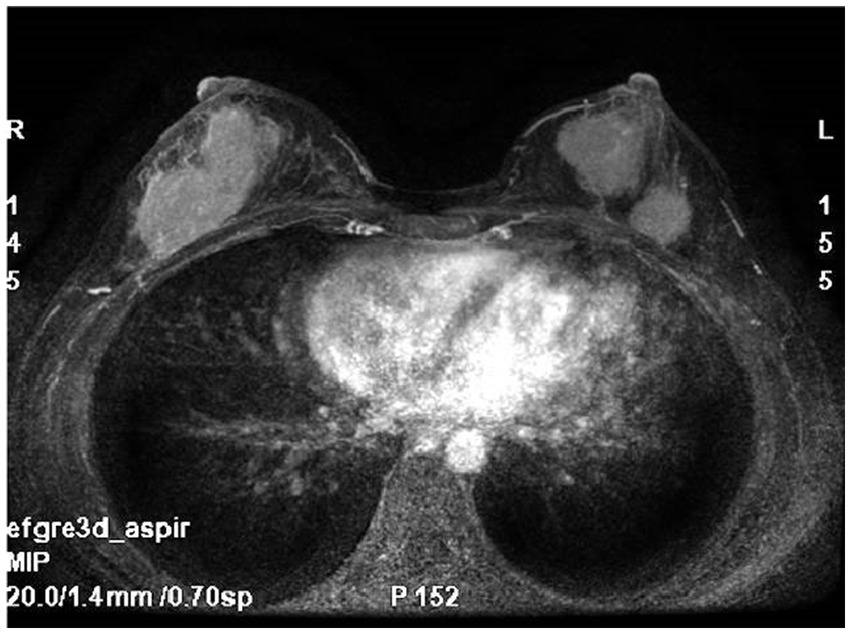

Breast MRI (Figure 1) with plain scan and enhancement revealed bilateral breast findings of type C, with low background enhancement, In the left breast, two masses with long T1 and short T2 signals were observed, both irregular in shape. The largest mass measured approximately 27 mm × 26 mm × 28 mm, with irregular edges and marked enhancement after enhancement. There was an increase in and thickening of surrounding blood vessels. The time signal curve was type II, and limited diffusion was noted. In the lower outer quadrant of the right breast, a quadrantally distributed enhancement lesion was seen, measuring approximately 61 mm × 30 mm, with increased and thickened surrounding blood vessels.

Figure 1

Breast MRI: bilateral breast mass, irregular shape, irregular edge, marked enhancement.